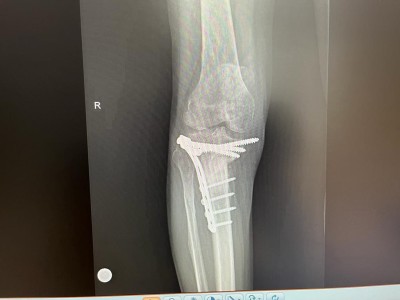

In cadrul sectiei de ORTOPEDIE – TRAUMATOLOGIE, s-a realizat cu succes o interventie chirurgicala cu grad ridicat de dificultate, la un pacient in varsta de 53 ani, care a suferit în urma cu aproximativ opt luni o fractura cominutiva bituberozitara de platou tibial cu intarziere în consolidare vicioasa.

In cele opt luni, genunchiul pacientului s-a deformat progresiv, materialul de osteosinteza a migrat generand dureri continue pacientului iar mersul fiind posibil doar cu cadru.

In acest context, deformarea severa a tibiei si calitatea slaba a calusului osos impuneau o interventie chirurgicala de protezare a genunchiului cu endoproteza de revizie. Aceasta a fost efectuata de catre echipa medicala condusa de dr. CHIREA MARIUS, medic primar ORTOPEDIE-TRAUMATOLOGIE.